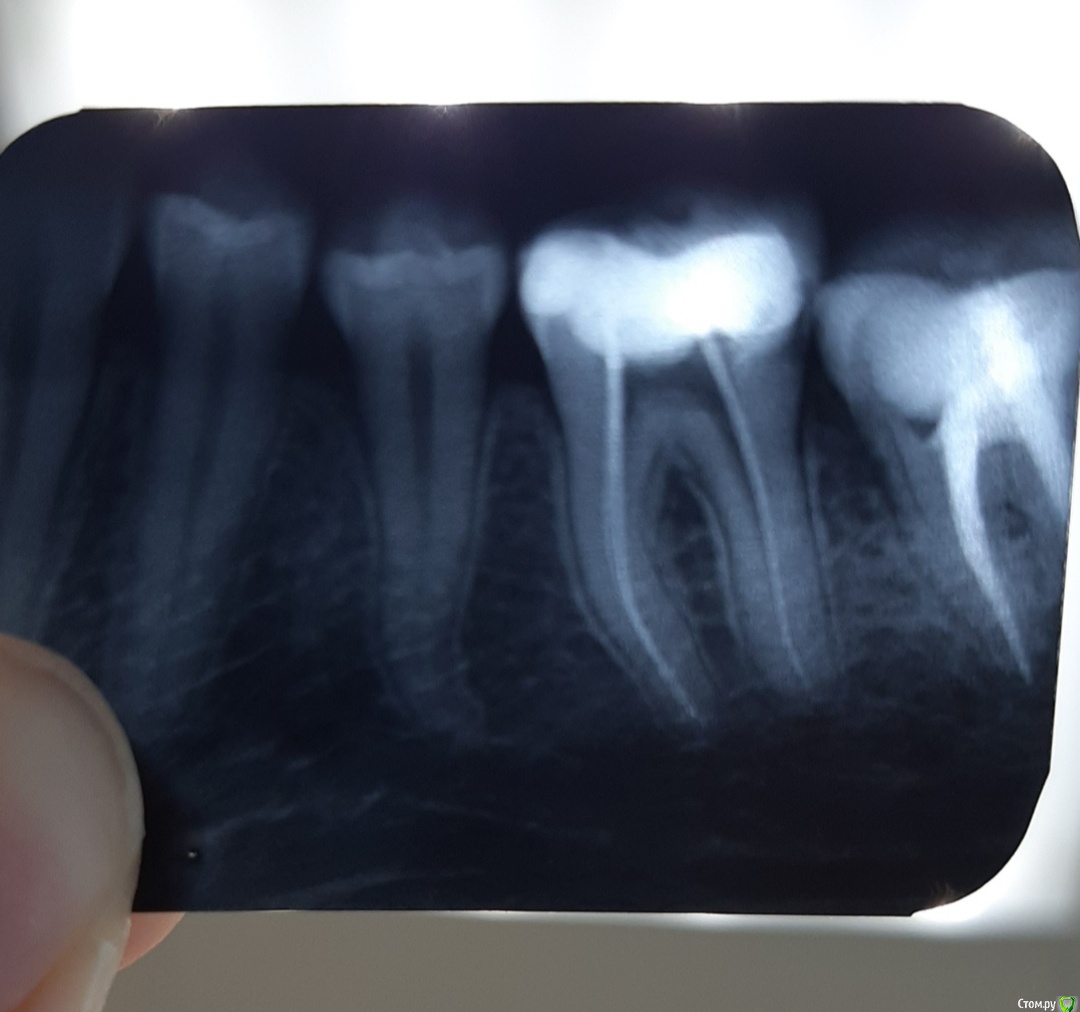

Аннушккка Опубликовано 8 мая, 2020 Поделиться Опубликовано 8 мая, 2020 удалили нерв в зубе слишком пломба давила на зуб, каналы не болели, но после пломбировки сильно стали болеть,еще сильные боли в десне между 5 и 6 зубом врач говорит что там нет ничего:но боли колющего характера,буд то туда тыкали иглой, я незнаю что делать помогите, вот сримок до пломбировки каналов.может моя проблема в других зубах рядом,или есть карман и он болит??? Ссылка на комментарий